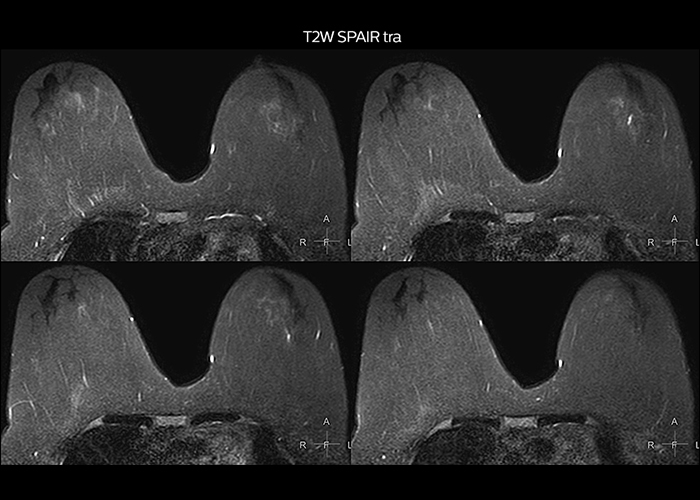

“On average, we scan about 80 patients per day, but on some days we scan well over 100 patients. The scanner is in use 7 days per week, operated 20 hours per day on week days and 8 hours per day in the weekend,” Mr. Tuna says. “To avoid coil changes we plan examinations of similar anatomies back to back, such as head and spine. Multiva helps us here a lot because coils don’t need to be changed frequently. Moreover, thanks to parallel imaging technology and 16-channel HeadSpineTorso and 8-channel MSK coils we are able to achieve excellent image quality. In this way Multiva helped us to increase both image quality and productivity.” “Neurological cases, such as brain and spine imaging, represent the largest share in our MR scanning, followed by musculoskeletal cases. In general, we use simple and basic imaging protocols. But occasionally, we use advanced techniques for problematic cases if necessary.